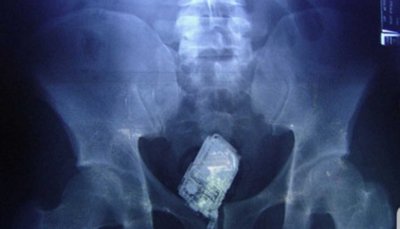

Acaip ha denunciado que "los funcionarios deben hacer frente a esta realidad con medios claramente insuficientes". Así, los terminales, cada vez más pequeños y fabricados con componentes plásticos, "escapan fácilmente a los detectores de metales y pueden esconderse en los lugares más insospechados". Esto obliga a realizar "requisas exhaustivas que requieren formación especializada y suficiente personal, algo que hoy en día no se garantiza en todos los centros".